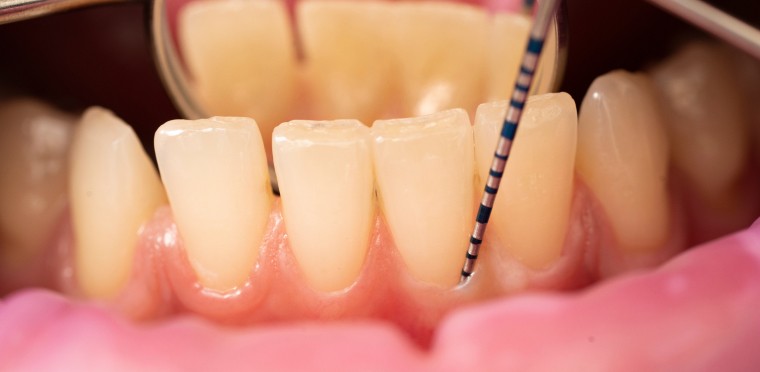

Bilan parodontal : Guide & Conseils

Surfaçage radiculaire : guide du traitement et conseils

Curetage dentaire à Toulouse

Curetage dentaire : ce qu’il faut savoir !

Poche gingivale : définition et traitements